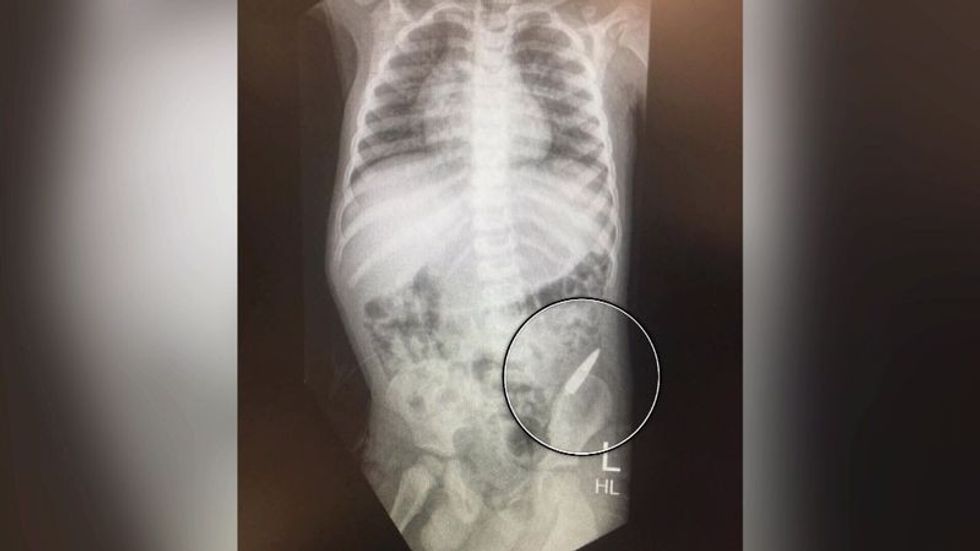

Sidoqoftë, ai është dërguar me urgjencë në spital, ku pas rëntgenografisë së bërë është konstatuar se plumbi ka ngecur në zorrën e trashë. Megjithatë plumbi nuk ka shkaktuar kurrfarë dëmi, kështu që mjekët nuk kërkuan ndërhyrjen kirurgjikale.